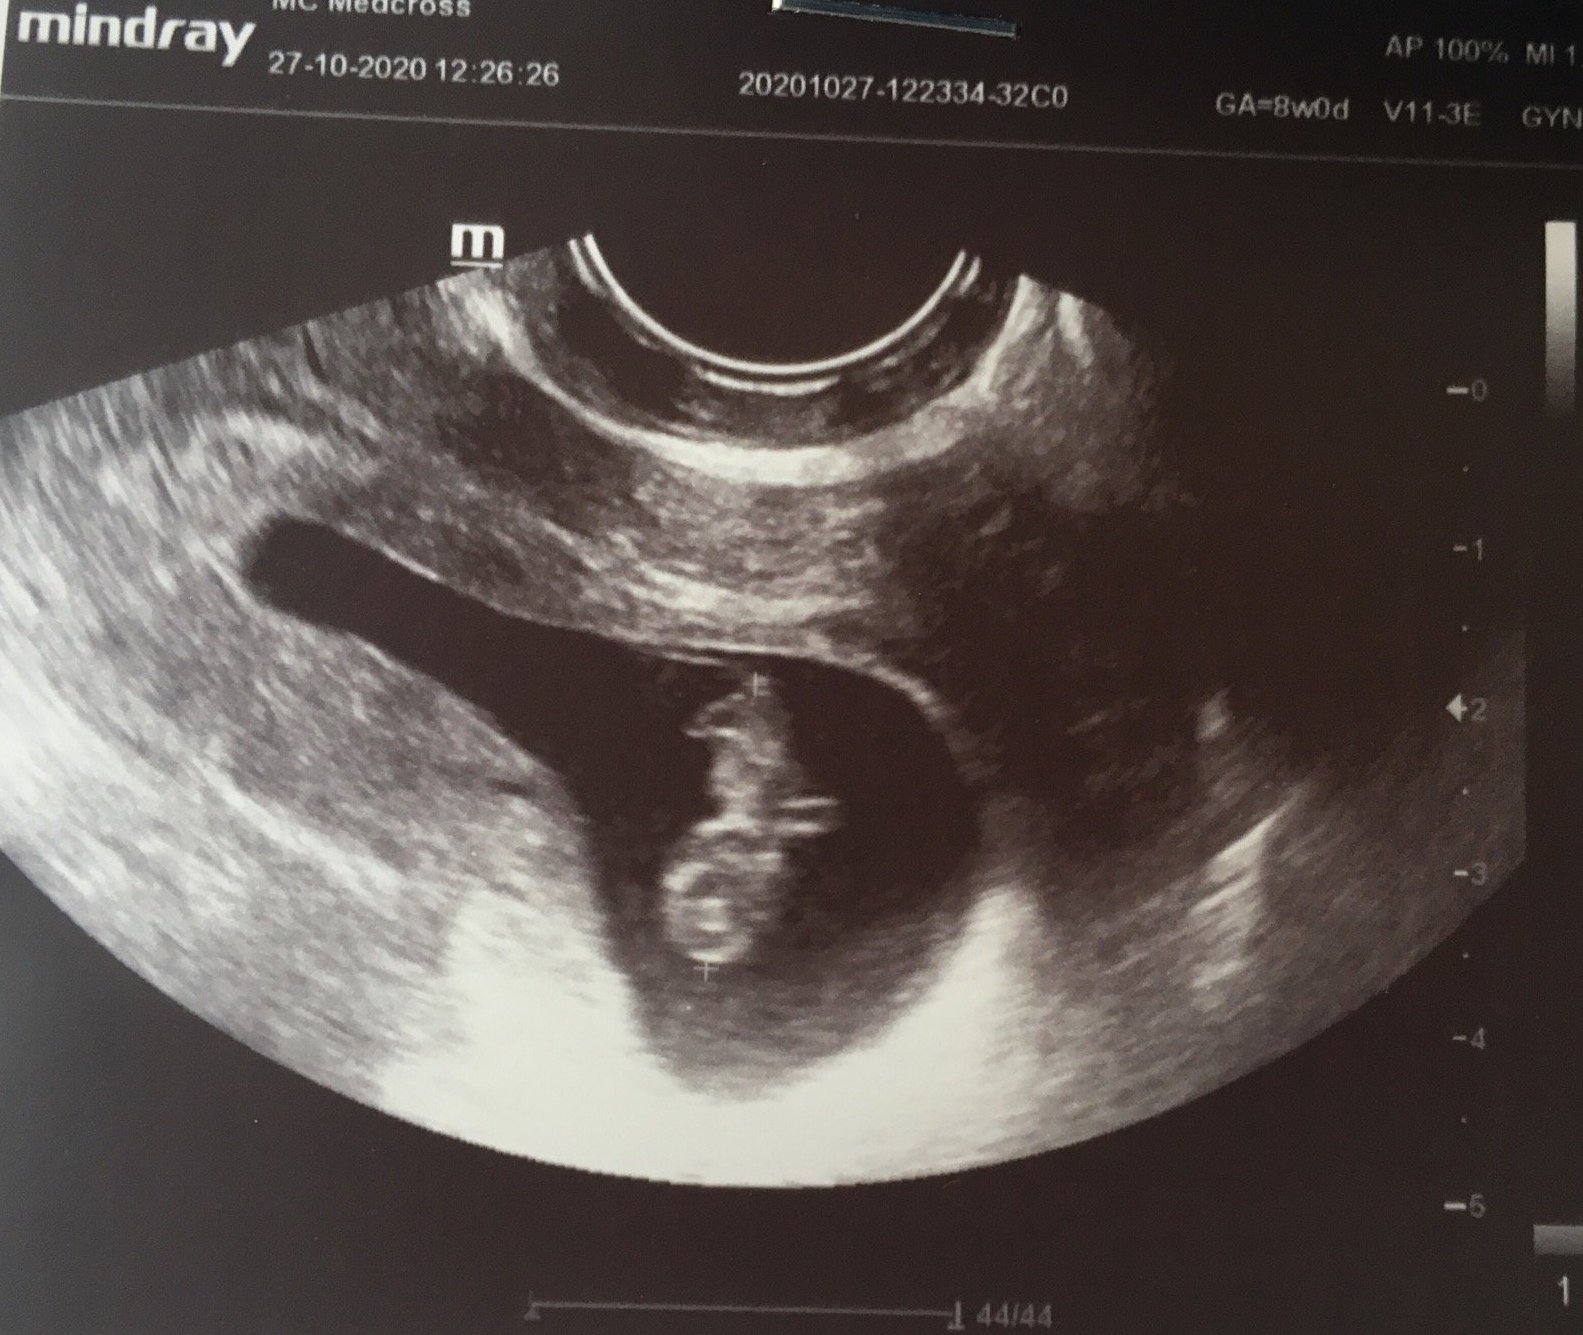

Моят сак също е малко по-дълъг, каза ми, че е възможно бременността да е була двуплодна и затова да е такъв, но сега има само едно бебче.